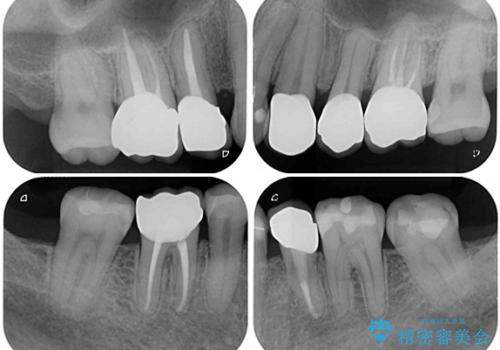

痛みは速やかに引き、銀歯や黒く変色したむし歯がセラミッククラウンで自然な色合いに仕上がり、患者様には大変満足していただきました。